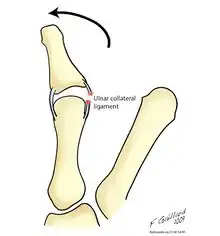

Gamekeeper's thumb and skier's thumb are two similar conditions, both of which involve insufficiency of the ulnar collateral ligament (UCL) of the thumb. The chief difference between these two conditions is that skier's thumb is generally considered to be an acute condition acquired after a fall or similar abduction injury to the metacarpophalangeal (MCP) joint of the thumb, whereas gamekeeper's thumb typically refers to a chronic condition which has developed as a result of repeated episodes of lower-grade hyperabduction over a period of time.[7] There are four types of Skier's thumb injury:[7]

In addition to skiing, this injury (resulting from forced abduction or hyperextension of the proximal phalanx of the thumb) is seen in a wide variety of other athletic endeavors. The most common mechanism of injury appears to be when a person extends the arm in an attempt to block a fall. The stress resulting from falling onto an abducted thumb produces a valgus force on the MCP joint of the thumb, resulting in a sprain or tear of the UCL.[8]

CS Campbell, an orthopedic surgeon, originally coined the term gamekeeper's thumb in 1955, after he observed this condition in a series of 24 Scottish gamekeepers.[10] The injury appeared to occur as a result of the particular manner in which they killed small animals such as rabbits; the animals were placed on the ground, and their necks were broken as the gamekeeper exerted downward pressure with the thumb and index finger. This maneuver would place a valgus force upon the abducted metacarpophalangeal (MCP) joint. Over time, this would lead to insufficiency of the ulnar collateral ligament (UCL) of the thumb.

The term skier's thumb is derived from the fact that skiers often acquire this type of injury by falling against a planted ski pole, tearing the UCL by hyperabducting it.[11]